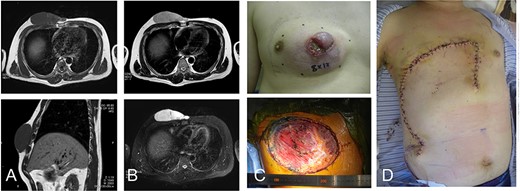

76-year-old male with recurrent myxofibrosarcoma. Computed tomography revealed the initial 6-cm subcutaneous lesion of the patient at 73 years of age (A); 3 years after resection of the initial lesion, T1- and T2-weighted images show a 3-cm recurrent lesion with high-signal intensities (B-upper) and (B-lower), respectively. Photograph showing protuberant subcutaneous lesion (C); defect after resection of the tumor with the surrounding tissue (D-upper). The defect was reconstructed with a thoracoabdominal flap (D-lower).

A 73-year-old man presented with complaints of a mass on her right chest wall for several months. Physical examination revealed a 6-cm elastic mass on her anterior chest wall that ranged from soft to hard on palpation. Computed tomography showed a subcutaneous tumor that was 6 cm in diameter (Fig. 2A). Histological examination of a biopsy specimen revealed a myxofibrosarcoma. The tumor was resected with the skin over the tumor, and the wound was closed without reconstruction. After 3 years of the initial operation, the 76-year-old patient underwent MRI, which revealed a recurrent lesion of 3 cm in diameter showing homogenous low-signal intensity on the T1-weighted image and homogenous high-signal intensity on the T2-weighted image (Fig. 2B).

The tumor was resected along with more than 4 cm of surrounding underlying pectoralis major muscle and the skin and subcutaneous tissue, resulting in a defect of greater than 12 cm in the maximum diameter. The defect was reconstructed by the same method used in Case 1 for placing a medially-based thoracoabdominal flap (Fig. 2C andD). The patient’s shoulder showed free range of movement. The patient has remained free of tumor over a 4.5-year postoperative period.